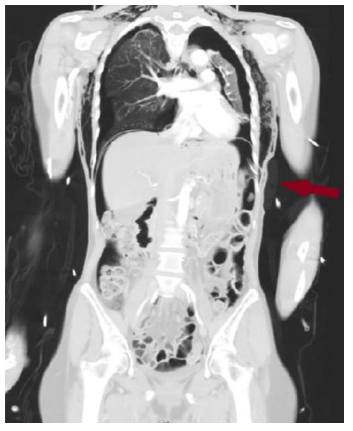

随后将患者转运至放射科行计算机断层扫描(CT),结果显示双侧气胸伴广泛性气腹(图2),口服造影剂外渗至腹腔,提示存在胃破裂。CT检查还显示左侧胸腔引流管位于腹腔内。CT扫描后立即于右侧放置胸腔引流管,可见气体即刻排出。